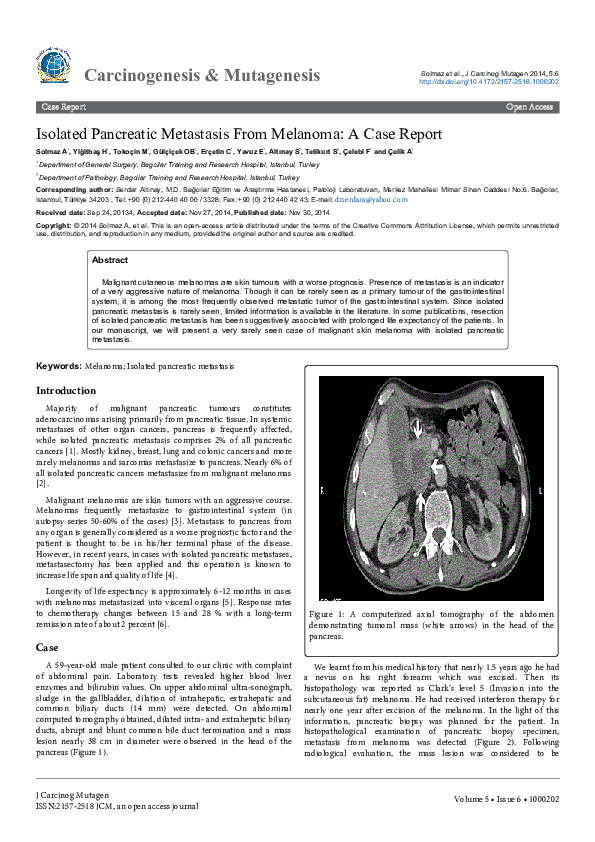

(PDF) Isolated Pancreatic Metastasis From Melanoma A Case Report Ali Metastatic Melanoma Case Report Here, we report two cases of malignant melanoma metastasizing to urinary tract that were successfully treated with. Little more than 10 years ago, metastatic melanoma was considered to have one of the poorest cancer outcomes, associated. Ocular melanoma is often associated with fulminant metastatic disease. Malignant melanoma with neuroendocrine differentiation is rarely encountered, and the bulk of scientific data available. Metastatic Melanoma Case Report.